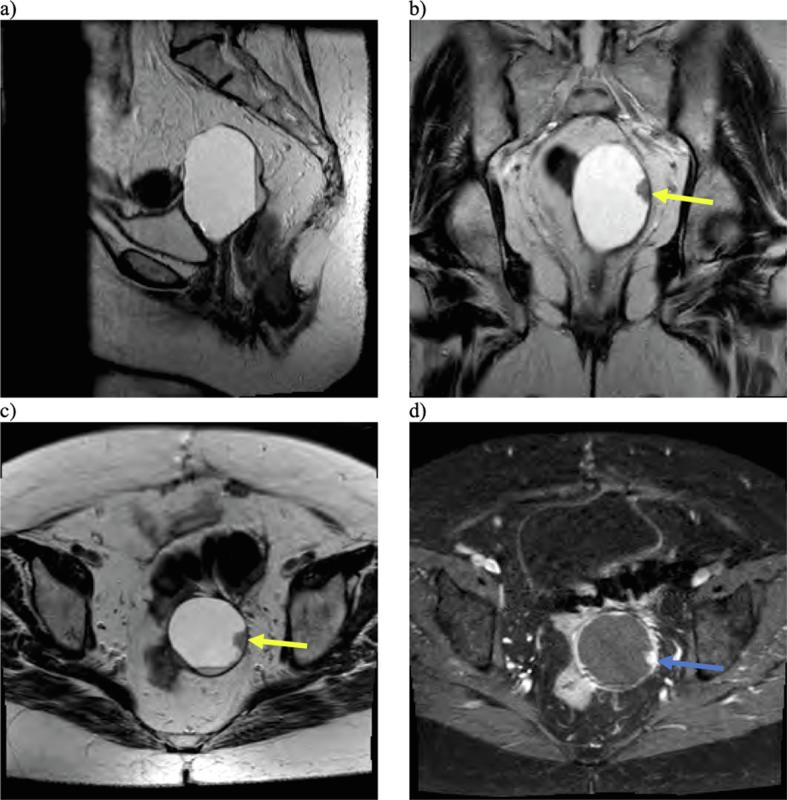

Fig. 1.

Multiplanar, multisequential MRI of the pelvis was obtained with T2-weighted sagittal (a), coronal (b), and axial (c) images demonstrating a cystic lesion arising from the vaginal cuff with peripheral nodularity (yellow arrows) and dependent debris. The area of nodularity also demonstrated enhancement on T1-weighted post-contrast imaging (blue arrow). (For interpretation of the references to colour in this figure legend, the reader is referred to the web version of this article.)

Over the next 2 years, she had an additional CT-guided drainage procedure (benign cytology) and a colonoscopy with biopsy of sigmoid colon ulcer (benign colonic mucosa with focal changes suggestive of ischemia). She was managed for a few months with oral progestin and experienced periods of time without symptoms, but began having abdominal pain 2 years after her most recent surgery, at which time she decided to pursue ethanol sclerotherapy treatments. She underwent 3 cyst drainage and ethanol instillation procedures, after which she developed a peritoneal-vaginal fistula. She was managed with topical estrogen initially and the drainage decreased, but she continued to have intermittent vaginal drainage and a 0.5 cm vaginal cuff defect was visible and monitored on physical exam. Nearly a year after her sclerotherapy treatments, an MRI revealed a 7.9 cm complex pelvic cyst with areas of enhancing nodularity (Fig. 1), characteristics that were unchanged from previous imaging over the past 4 years. The impression was that of a recurrent peritoneal inclusion cyst. She was closely monitored with serial exams, and 1 year later, vaginal cuff biopsy was consistent with chronic inflammation with hemosiderin deposition but negative for malignancy.